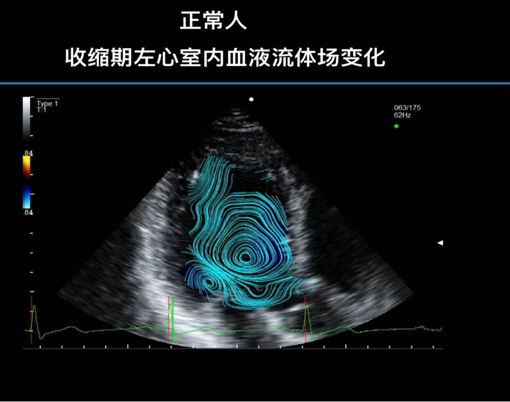

我国一直是风湿性心脏瓣膜病全球高发国家之一,全国风湿性二尖瓣患者每年仍然平均占比心脏外科二尖瓣病变住院治疗人群的40%左右,面对每年心脏外科风湿性二尖瓣远高于95%以上是以人工瓣膜置换为治疗手段的现状,认真思考对于风湿性二尖瓣修复技术的认知与应用可行性的讨论,关系到千万患者的切身利益也是中国为全球风湿性二尖瓣治疗技术提升该有的担当。一·二尖瓣装置的完整性是心脏核心功能维护的基石心脏功能的好坏通常是指左心室的收缩状态,即左心室的“泵血”功能;二尖瓣作为左心室的第一瓣膜“阀门”,其解剖及生理形态的装置整体(二尖瓣环,二尖瓣体,二尖瓣腱索,二尖瓣乳头肌)完好直接决定着左心室“泵血”的做功状态及效能,其原因可以从以下几点予以说明:1·左心室接受左心房血液充盈时,在二尖瓣生理架构完整情形下是呈现“横向”扩张,这是左心室最佳的前负荷状态表现,左心室心肌细胞内参与心肌收缩的肌桥数目最多,是左心室收缩开始的最佳“预备”;如果二尖瓣生理架构由于人工瓣膜置换而遭到破坏,左心室充盈形态便会呈现为“纵向”拉长,无法达到理想前负荷状态,就像跳远者失去助跑距离和短跑赛者没了起跑器。2·左心室的收缩具有“序列性”和“螺旋性”两个生理特性,即左心室收缩是有各部位心肌在时间先后和空间近远与方向的程序规律协调的特性,左心室在心脏电生理的启动下各部心肌序列收缩并借助左心室解剖上的螺旋心肌带形成左心室“绞结”产生“拧手巾”样的收缩“泵血”过程。二尖瓣装置最终是通过二尖瓣乳头肌链于左心室壁,是左心室序列及螺旋性收缩形成的重要组件,二尖瓣人工瓣膜置换导致二尖瓣生理架构异常必然弱化左心室收缩的序列不良和螺旋绞结力下降。3·良好完整的二尖瓣装置下,左心室血液流场研究的初步探讨证实,左心室在收缩早期可以借助二尖瓣装置使得左心室血液在进入体循环前先行在心室内形成较大的血液涡流现象,这种血液涡流状态是左心室血液克服前向阻力进入大血管的重要动能之一,因为“涡流”形成必然伴随抛物线动能产生,犹如铁饼投掷前的自身转体加速。所以左心室的“泵血”动能应该是包含心室肌收缩和心室内生理血液涡流两个元素组成,而在二尖瓣装置破坏(人工瓣膜置换)及病变条件下,血液流场研究可以显示这种生理性血液涡流明显紊乱碎裂甚至消失,如此左心室“泵血”只能单一依靠心肌收缩完成,当然就使得心脏做功及消耗增加长此以往心脏功能的慢性衰竭是难以避免。我们初步的左心室内血液流场图,可以直观的呈现给大家正常人,风湿二尖瓣病变时的血液涡流状态;另外也通过正常人,风湿二尖瓣修复后,风湿二尖瓣人工机械瓣置换后和风湿二尖瓣人工生物瓣膜置换后左心室内血液涡流状态的对比,提示二尖瓣修复的重要性。总之,希望无论是否是专业或非专业人士也包括我们的患者能够通过前述表达,理解二尖瓣装置生理架构的完整是心脏功能维护的基石,二尖瓣装置被人工瓣膜替代可能是心脏功能慢性不良的开始,这也说明为什么在全球范围都在倡导二尖瓣病变要修复为主的原因,说明为什么几十年来临床实践和相关医学证据都在表明二尖瓣修复术后患者在各时期环境下生存空间生存质量明显好于人工瓣膜置换技术。二·质疑风湿性二尖瓣修复若干论点的辨议二尖瓣修复临床疗效远好于人工瓣膜置换应该说早以成为世界心脏瓣膜专业治疗领域的共识,但客观现实是二尖瓣修复技术是否适合风湿性二尖瓣外科治疗,至今仍处于争议状态并且持续了约30年。回首这种争议应该归纳到两个层面,一个是认识理念一个是应用技术的突破。认识理念指的是风湿性二尖瓣修复是不是可以复制出非风湿性二尖瓣修复优于人工瓣膜置换的循证医学证据,技术层面则因为风湿性二尖瓣病变是整个装置的侵及,技术细节无规则无规模无认同。科学道路上争议往往是推动某个问题深入探讨并使得问题得以提升的助推器,风湿性二尖瓣修复在技术层面即使再难也是可以通过交流,研究学习和实践来提升改善的,终归是一种外科“肌肉记忆”的相对容易的技能体验与专业悟性较量;而认知理念的差异才是影响我们正确感知事物本质及决定事物走向如何的核心要素,决定了我们是不是有激情,是不是该坚持,是不是能担当;希望我们通过以下观点的讨论或争议来更多的促进对风湿性二尖瓣修复理念的正确认知。1·风湿热未必是风湿性二尖瓣修复技术疗效的影响因素风湿热所致的自身免疫性损害是心脏风湿性二尖瓣病变的罪魁也是推动病变进展的魔手,所以即使风湿性二尖瓣修复的再好也会由于持续风湿热侵害而丧失治疗意义。在如此颇有道理的所谓常识里,大家忽略一个重要事实,风湿热发病有什么特点吗?风湿热发病与患者年龄环境等时空变化的规律是什么?风湿热活动期是会伴随患者终身吗?事实是早在上世纪八十年代就有定论,风湿性二尖瓣患者伴随风湿活动期主要集中于部分年轻群体而且大多数情况下不会与患者相伴终生;对于当时的大宗心外科闭式扩张手术病例二十四年观察,每年风湿活动发生率仅为0·13%~0·22%,2020年国际多个应用长效青霉素进行抗风湿治疗指南标明对于大多数患者停止用药的年龄是<35岁;另外一个情况是我国风湿性二尖瓣入院患者血液学检查总体风湿活动很低(<10%)而在40岁以上病例中几乎为零。风湿活动不会伴随患者终身,至少大多数25~35岁以上的风湿性二尖瓣患者应用修复技术治疗是不会因为风湿活动影响疗效,仅因为风湿活动来质疑风湿性二尖瓣修复技术是不很科学的观念。2·纠结风湿性二尖瓣修复的再手术实为“芝麻与西瓜”的错位误导“风湿性二尖瓣手术就两种方法,一个是修复但会面临二次手术可能,一个是换人工瓣膜,请你和家属做好选择…”这是每个风湿性二尖瓣患者在手术前谈话或签字时,在做对于手术方式选择时被医务人员告知的信息,内容几乎在中国的所有医疗中心竟是如此一样,说到二尖瓣修复一定会带出“再手术”的警告,而说到人工瓣膜置换却是无言之中“一劳永逸”的潜含…问题是作为患者至上的职业精魂,我们只有将事物的完整信息正确传递给每一个患者才应该是对这份职业的尊重;完整的信息应该基于几个重要事实,修复治疗与人工瓣膜置换治疗是不是都有再手术问题?修复手术的再手术几率在不在可接受范围?修复手术与人工瓣膜置换手术在生存空间的差异有多少?面对治疗后修复可能再手术几率高些与人工瓣膜置换生存几率可能低些的客观矛盾中该如何考虑权重及优先?我们可以基于以下的证据做些阐明:(1)风湿性二尖瓣修复手术和二尖瓣人工瓣膜置换手术均有二次再手术风险。通常二尖瓣修复后再手术发生率是二尖瓣人工瓣膜置换后的二倍左右;依据2013~2021年发表的几篇Meta分析及大宗病例报道,风湿性二尖瓣修复治疗后十年再手术率约3~6%,其中有一篇综合Meta分析将风湿性二尖瓣手术不同方式依照十年再手术几率从高到低排位,依次是风湿性二尖瓣人工生物瓣膜置换,风湿性二尖瓣修复和风湿性二尖瓣人工机械瓣置换。风湿性二尖瓣修复的再手术率并非是榜首,但是以十年修复术仅平均5%的再手术率作为对患者选择的警告和唯一告知,是不是反映出明显带有对风湿性二尖瓣修复认知的偏见?(2)心脏瓣膜外科在评价一种治疗方式时通常以围手术期死亡率,远期生存率,治疗后长期不良事件(并发症)发生率和远期再手术率四个指标作出综合性疗效评价。在这四个指标中,前两个指标是直接与生存死亡相关,后两个指标主要反映患者生存质量只是相对间接关联生存。我们仍然以近年Meta和大宗文献数据为依据,对比风湿性二尖瓣修复与风湿性二尖瓣人工瓣膜置换四个指标,结果是风湿性二尖瓣置换手术围手术期死亡率是二尖瓣修复手术的2·6倍,风湿性二尖瓣人工瓣膜置换手术远期(10年)死亡率约是修复手术的4倍,风湿性二尖瓣人工瓣膜置换手术后远期不良事件发生率是修复手术的3倍。如此下来,风湿性二尖瓣修复手术在四个评价指标有三个处于绝对优势,虽然再手术率十年5%几率应该得到重视,但起码患者是活着,在一个生存更保障只是可能会经历再手术与一个可能远期生存保障有问题的风险的抉择中,显然再手术是个“芝麻”而“生存”才是西瓜,我们不能错位选择。3·国际风湿性二尖瓣治疗的“球囊”指南难以契合中国国情中国有众多的心脏病患者,但是发展中国家国情难以形成理想的科学研究氛围是现实,我们有的是治疗患者的数量却乏有治疗患者的数据(全国心脏外科手术后三年以上随诊率估计不足30%)自然中国的治疗指南无从谈起;心脏病治疗长期以欧美发布的治疗指南为纲是常态,但是仅就风湿性二尖瓣欧美指南内容而言,其中国的适应性应该值得思考。2020年欧美针对风湿性二尖瓣治疗的指南阅后,总结出几个感触:(1)欧美指南基本是个基于介入二尖瓣球囊扩张的指南,明确有扩宽球囊扩张适应指征倾向。这个倾向与源于对心脏外科风湿性二尖瓣治疗长期仅停留在人工瓣膜置换单一技术方式的现实直接相关。对于心脏外科在风湿性二尖瓣修复技术进展存在认识瓶颈。(2)参与撰写作者里只有一位心外科专家,指南内容所涉及心脏外科相关引用文献普遍超过40年。(3)心脏外科风湿性二尖瓣修复首次正式有对近远期综合疗效好于球囊扩张技术的文字认可,但显然把风湿性二尖瓣修复这项技术归纳为只是某些医疗中心或专家的“曲高和寡”之作。(4)对于风湿性二尖瓣患者心外科治疗时机,指南是在介入球囊扩张失败或禁忌前提下,患者二尖瓣病理病变严重同时伴随临床症状严重,以适合二尖瓣人工瓣膜置换技术定义为判别标准的治疗指南,是个外科治疗手段完全时机滞后的治疗指南。应该看到,风湿性二尖瓣病变在欧美区域发病率很低,风湿性二尖瓣患者占比二尖瓣病变治疗主体非常小,欧美心外科医生基本没有风湿性二尖瓣除去人工瓣膜置换以外的治疗经验和经历,如此情况下强调介入二尖瓣球囊扩张技术权重当在情理之中。问题是中国风湿性二尖瓣患者是常规治疗群体,在我们患者医疗教育及医疗信息获得不畅或有限,社会保障体系远没有发达国家健全,就医环境医疗资源区域差异很大的具体国情下,机械参照欧美指南的介入球囊扩张技术应用,滞后外科治疗参与的观念应该引起质疑。回首近十年风湿性二尖瓣球囊扩张技术应用比例全球是大幅降低的,同时相关治疗后并发症增加的数据更得到关注;中国二尖瓣球囊扩张技术应该更加慎重应用,理由是:(1)指导二尖瓣介入球囊扩张的术前评估体系WilkinsScore存在明确的判别误差或局限,无法与风湿性二尖瓣病理改变成都相匹配,即WilkinsScore分数的高低与外科直视观察二尖瓣病变程度乏有线性关联;而且多年来WilkinsScore大于5分后的特异性或者准确性早已经是受到业内广泛质疑。如果判定标准有质疑,那么治疗指征何谈?精准何谈?疗效何谈?(2)正因为球囊技术应用前的判定标准问题也必然带来临床球囊技术治疗后的另一个事实,即二尖瓣球囊扩张大部分结果是风湿性二尖瓣体组织局部撕裂,而非是二尖瓣狭窄遵照二尖瓣解剖生理交界自然走行的瓣口开放。二尖瓣球囊扩张以二尖瓣体组织撕裂带来的“瓣口面积”所谓获益只是表面短时的,风湿性二尖瓣狭窄有瓣口狭窄和瓣下狭窄,而球囊扩张是无法缓解瓣下狭窄,于是二尖瓣狭窄导致的流经二尖瓣进入左心室的异常血流状态仍然存在,这种异常血流仍将继续“咬噬”二尖瓣装置推动着二尖瓣体组织病理性恶化的进程。证据是临床上球囊扩张后心外科直视看到的患者二尖瓣病变的现象是在球囊扩张痕迹局部二尖瓣体组织增厚更剧,纤维变性更重,产生钙化范围更广,瓣下结构融合更多。目前国内风湿性二尖瓣球囊应用随世界应用下降,我国心脏超声的WilkinsScore的评价体系质量控制水准也应该重视,很多风湿性二尖瓣患者更是在无评分情况下被“介入球囊”微创治疗的概念绑架,不清楚这种姑息性治疗方式存在着潜在的二尖瓣组织,心脏功能和心肺功能慢性损害,不知道有可能失去心脏外科最佳治疗时机,失去最佳二尖瓣修复几率等诸多治疗红利的悲哀。盲目性跟从的风湿性二尖瓣球囊扩张治疗应该纠正,面对中国国情建立心脏内外科融合治疗体系共同探讨设置中国风湿性二尖瓣治疗规范应该进入日程。三·修复技术面对国人风湿性二尖瓣病理特征难有应用实效之辨议有了对风湿性二尖瓣修复治疗理念的融通,则风湿性二尖瓣病理病变程度与修复方式的适用性只是个轻松的技术层面探讨。风湿性二尖瓣全球分布集中于经济欠发达区域,患者的生活文化氛围及就医环境也印证出不同地区风湿性二尖瓣病理变化特征与差异;另一方面,风湿性二尖瓣病理损害是整个二尖瓣装置的累及(瓣体,瓣环,瓣下腱索与乳头肌都可能有不同程度损伤与改变),而非是像退行性二尖瓣病变以局部病理损害为主。应该说从理论和常理上,风湿性二尖瓣的病理损害程度一定是和修复技术的应用难度及可行有效密切相关的;而且由于风湿性二尖瓣是累积二尖瓣整个装置,想运用修复技术去矫正整个装置的病变,完全复原达到“整旧如新”“修好如初”,诸如使得僵硬增厚瓣体恢复柔软如绵,短缩形变腱索重新韧弹自如等根本就是不能实现的奢望;由此可见,认为二尖瓣修复技术移植于风湿性二尖瓣应用的非“完美”性,得出风湿性二尖瓣修复治疗不过是重姑息性手段的观点似乎很在理,是常理的思维逻辑。那么,中国患者目前风湿性二尖瓣病理表现或特点的真实世界是什么?二尖瓣修复疗效是应该以“修好如初”为标准吗?风湿性二尖瓣修复是否在技术运用上必须要做成“整旧如新”呢?如果风湿性二尖瓣修复治疗后在血流动力学标准方面达到或超过人工瓣膜置换,虽然“颜值”差点大家可不可以从情感上接纳或接受呢?面对如上疑问,提出如下的工作汇报供大家思考:(1)作者团队经过三年多对中国风湿性二尖瓣病理状态的研究,依据风湿性二尖瓣体及瓣下结构病变异常程度并结合心外科风湿性二尖瓣修复技术运用难易情况,将风湿性二尖瓣病理损害由轻至重分为I,II和III的风湿性二尖瓣修复病理分型,也就是说将风湿性二尖瓣病理严重程度和风湿性二尖瓣修复可行性及有效性进行了统一评判,也应该很符合前述的常理思维需求。结果是:风湿性二尖瓣轻度I型患者占比约15%,其运用团队推荐的风湿性二尖瓣“四步法”修复技术治疗成功率几乎100%;风湿性二尖瓣中度II型患者占比约65%,其运用团队推荐的风湿性二尖瓣“四步法”修复技术治疗成功率约为70%;风湿性二尖瓣重度III型患者占比<20%,其运用团队推荐的风湿性二尖瓣“四步法”修复技术治疗成功率约为30%.虽然这只是一个团队工作的数据,但还是可以说明一个事实,即中国风湿性二尖瓣患者的病理表现或真实世界是:严重病理病变,难以运用修复技术达到治疗效果的患者比例不是大多数。那么在对风湿性二尖瓣修复可行性的认可时,将仅仅约20%的重症病理的小众结果去否定约70%的大众运用二尖瓣修复技术成功几率显然有失科学;反映的不是技术层面的难易探索而是某些固有观念的偏执。这些团队工作数据还提出了一个重要启示:中国起码应该做到风湿性二尖瓣修复占比50%。(2)风湿性二尖瓣病变是二尖瓣装置全累积,存在明确个体差异性,风湿性二尖瓣修复是否必须“修复如初”?我们的明确答案应该是“No”。风湿性二尖瓣病理改变有着明确的规律及特征,全二尖瓣装置病变累及是表象,核心实质是a.二尖瓣交界区域纤维斑块融合导致的瓣膜口狭窄及关闭不全b.二尖瓣下继发前者异常血流产生瓣下结构融合形成的瓣膜下狭窄。鉴于此,如果我们的修复技术针对性运用,重点缓解或矫正上述的两个核心病理改变,以实现二尖瓣开合基本功能为目标,而不去纠结是否能“修好如初”的极致,结果是如何呢?实践表明,针对风湿性二尖瓣核心病理改变进行重点操作的风湿性二尖瓣”四步法“技术,无需”修复如初“,患者虽然还留有一些诸如二尖瓣缘增厚,某局部后叶瓣体及瓣下运动不良的弱颜值现象,但是并不影响风湿性二尖瓣”四步法“修复后的二尖瓣血流动力学指标,以目前全世界最大组风湿性二尖瓣修复与人工瓣膜置换配比研究的数据,二尖瓣修复后瓣膜平均开口面积约2·4cm2(人工瓣膜置换约2·2cm2),二尖瓣修复后跨瓣膜压差仅4mmHg(人工瓣膜置换约8~10mmHg)。事实是,风湿性二尖瓣修复不必”修复如初“是可以达到接近正常二尖瓣血流动力学标准,以超越人工瓣膜置换的数据,实现患者二尖瓣功能性治愈的目标。结语可能我们要面对中国风湿性二尖瓣患者治疗环境的诸多不如意,可能所谓”拙劣的修复远不如踏实的人工瓣膜置换“是如此的给你安慰,但是我们既然尊崇”患者为上“,那么努力为每一个风湿性二尖瓣患者争取修复机会是不是值得?中国现状风湿性二尖瓣修复比例仅1%左右,我们努力争取改变,做到10%,30%,50%…应不应该?请同意,推动风湿性二尖瓣修复理念和技术应该是作为心脏瓣膜专业医生必须的责任也是必然的担当。最后引用一句话与大家共勉:“不被看好是常态,人们往往要先看见才会相信,但总有些人因为相信所以看见”。